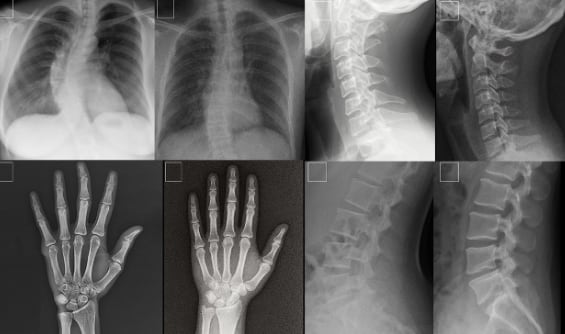

Imágenes de rayos X falsas generadas con inteligencia artificial fueron capaces de confundir a expertos, con “riesgos significativos”.

El estudio indicó que las imágenes fueron diseñadas para imitar con precisión los resultados clínicos de pacientes reales. Esto no solo puso en evidencia la capacidad técnica de estas herramientas, sino también su potencial uso malintencionado, ya que pueden engañar tanto a radiólogos experimentados como a otros sistemas de inteligencia artificial.

En la investigación, 17 radiólogos de 12 hospitales en seis países analizaron un total de 264 radiografías. La mitad de ellas había sido generada por herramientas como ChatGPT o RoentGen.

Los resultados fueron reveladores: cuando los especialistas no sabían que estaban frente a un experimento, solo el 41 % logró identificar correctamente las imágenes falsas. Sin embargo, una vez informados de la presencia de contenido sintético, la precisión aumentó al 75 %, según el informe publicado en Radiology.